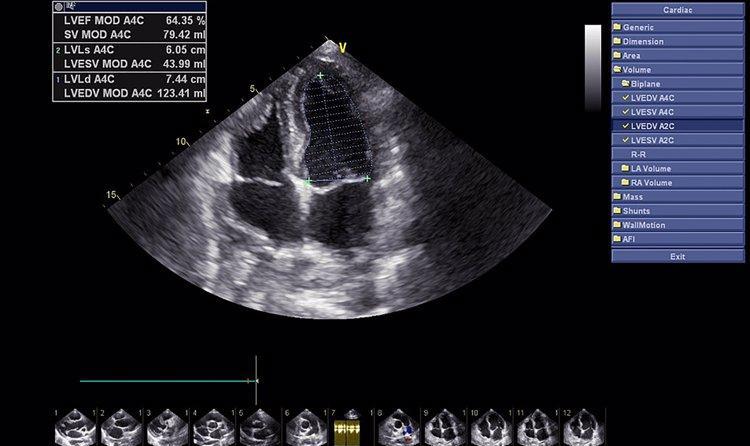

妇科检查项目中,有三项是女性必须要做的,绝不能忽略。首先是阴道分泌物检查,这可以帮助医生判断是否存在阴道炎症等问题。其次是肿瘤标志物检查,通过抽血检测肿瘤标志物的数值,可以发现一些潜在的问题,比如子宫内膜异位症、盆腔炎等。最后是妇科B超检查,通过这个检查可以了解子宫内膜的情况以及是否存在异常回声等问题。